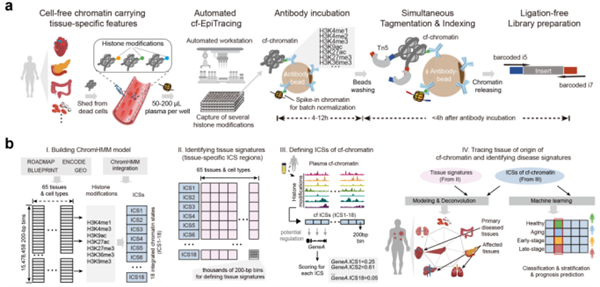

北大新突破:一滴血 查清病从哪来

最近,北京大学何爱彬团队联合多方合作者在国际权威期刊发表最新研究成果。 他们研发出具有自主知识产权的新一代表观液体活检技术cf-EpiTracing,实现仅靠少量血浆样本,就能精准识别病变来源组织、发现早期病2026-03-09 -